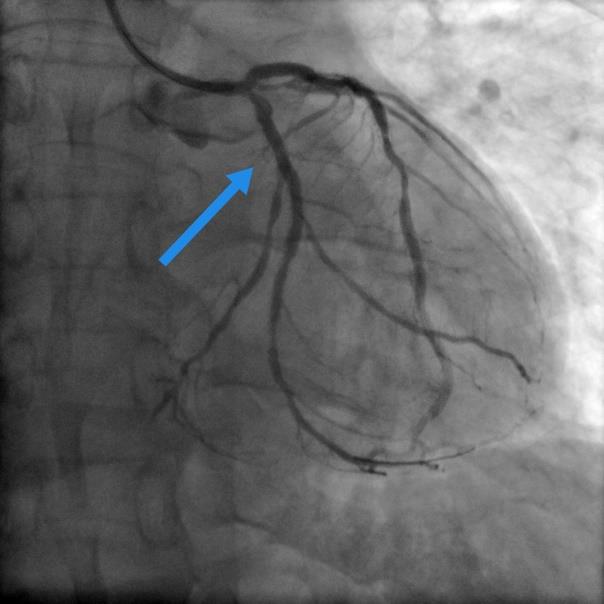

左图术前旋支狭窄95%(箭头处),右图术后狭窄完全消失。